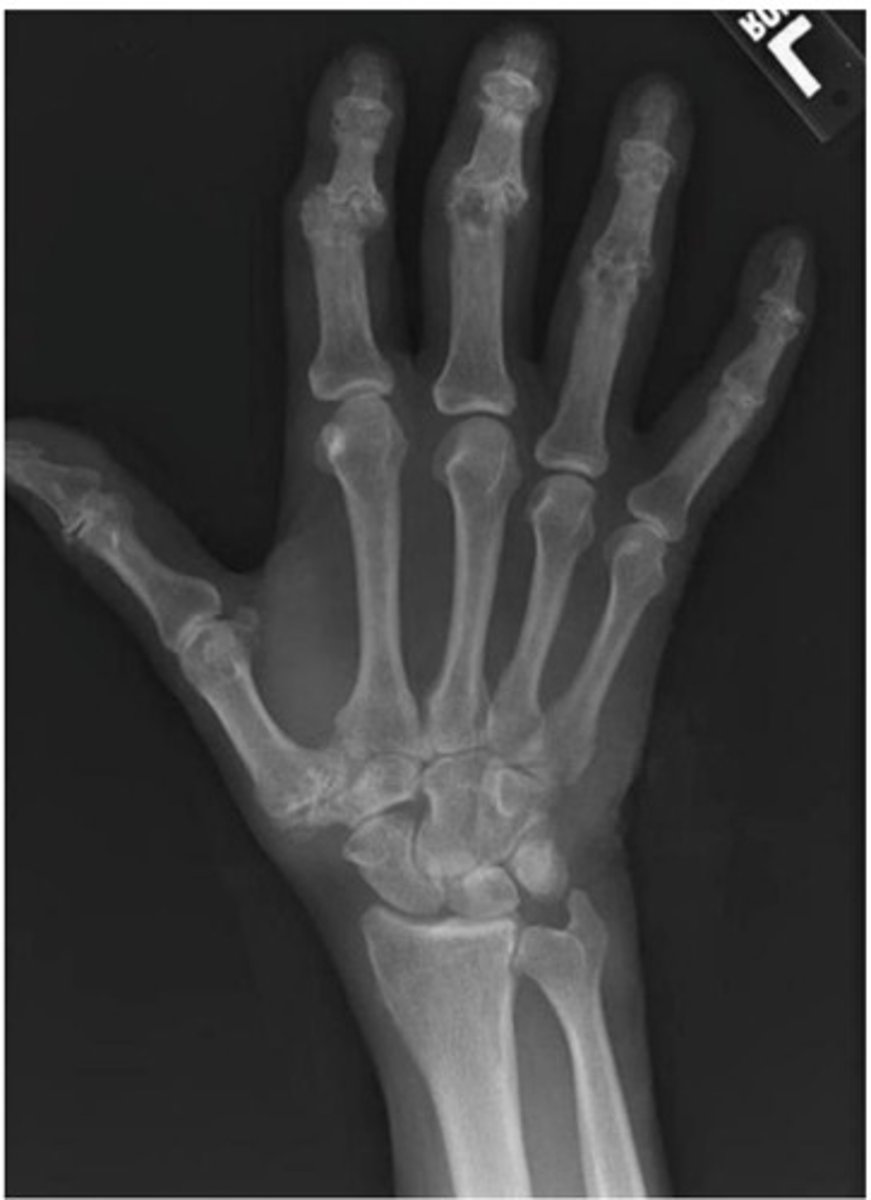

What diagnosis is this?

Rheumatoid arthritis